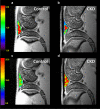

The purpose of present study was to longitudinally investigate the alterations in infrapatellar fat pad (IPFP) vascularity in 5/6 nephrectomized rats by using dynamic contrast enhanced (DCE) MRI and IPFP degeneration by using MRI T2* relaxation time. Twelve male Sprague-Dawley rats were assigned to a control group and a 5/6 nephrectomy CKD group. The right knees of all rats were longitudinally scanned by 4.7 T MRI, and serial changes in the IPFP were assessed at 0, 8, 16, 30, and 44 weeks by DCE-MRI (parameters A, kel and kep) and MRI T2* mapping. After MRI measurements, knee specimens were obtained and evaluated histologically. The CKD group had IPFPs with lower blood volume A and lower permeability kep values from 16 weeks (p < 0.05), lower venous washout kel value from 30 weeks (p < 0.001), and significantly higher T2* values reflecting adipocyte degeneration beginning at 16 weeks (p < 0.05). The histopathological results confirmed the MRI findings. Hypoperfusion and adipocytes degeneration related to CKD were demonstrated in a rodent 5/6 nephrectomy model. DCE parameters and MRI T2* can serve as imaging biomarkers of fat pad degeneration during CKD progression.